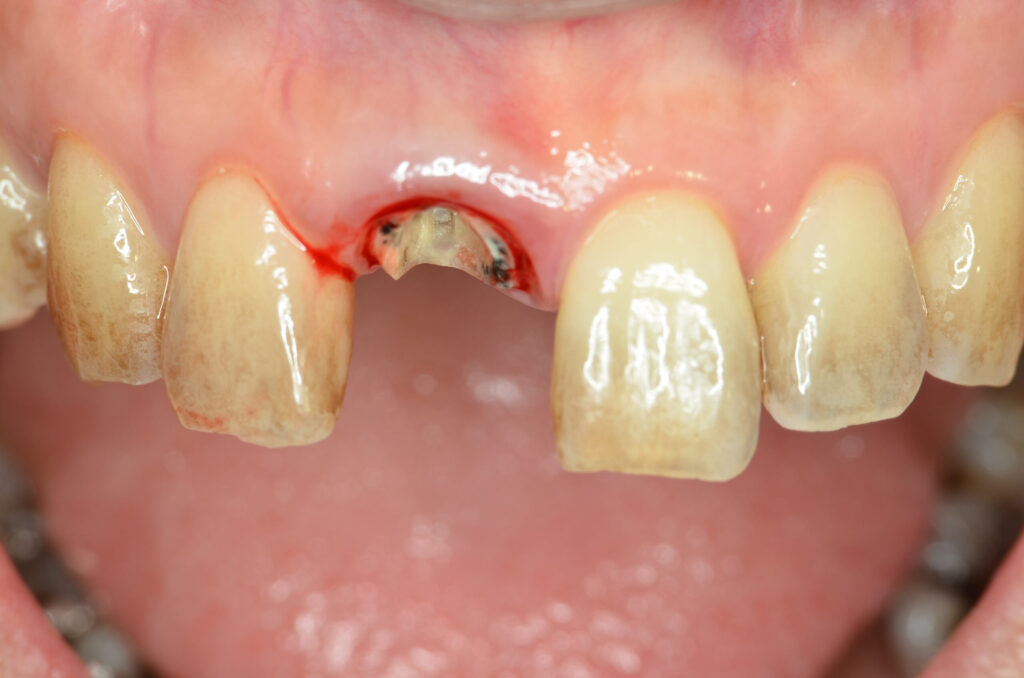

Before

治療内容

インプラント1本・骨造成・歯肉移植

治療のリスク

外科手術が必要になるため、患者様に体力的な負担がかかる。